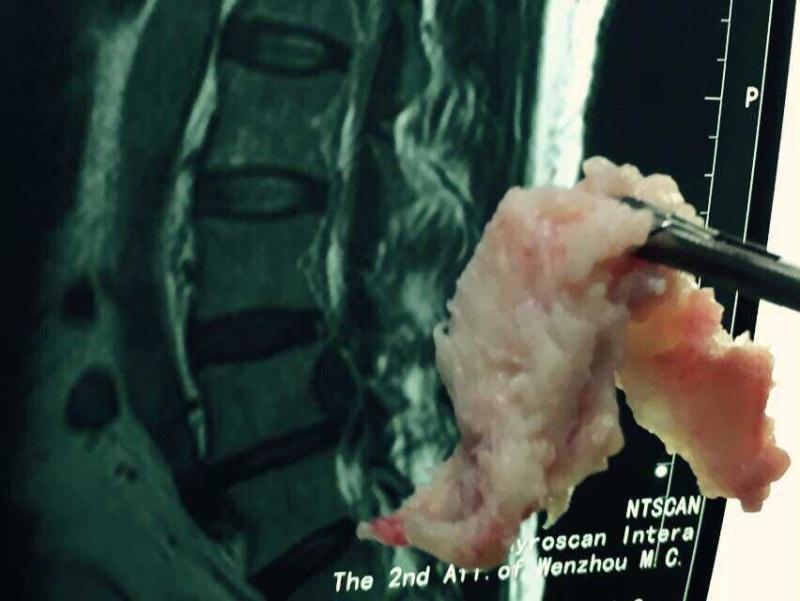

占主任仔细地看了看片子,发现金阿姨腰部有一节腰椎间盘突出,磁共振下的突出物像一堆泥石流滑坡压住神经根。占主任说:临床上老人因为家务事繁忙劳累得病的很常见,但在以前的确是只有开刀手术才能除根,近几年有了微创技术,只需吸管口大小的切口就能拿掉致病的髓核,达到治愈的目的。针对金阿姨的病情,占主任为其制定了德国椎间孔镜微创摘除术的手术方案。该技术只需在患者腰侧病变部位开一个仅仅5-7毫米吸管口左右大小的手术切口,把细小的孔镜放进去就可以在电脑屏幕上看到腰椎里面的血管、神经组织,然后突出的髓核就很容易的被钳夹出来,自然而然神经压迫就解除了,各种腰痛腿麻症状也会消失。